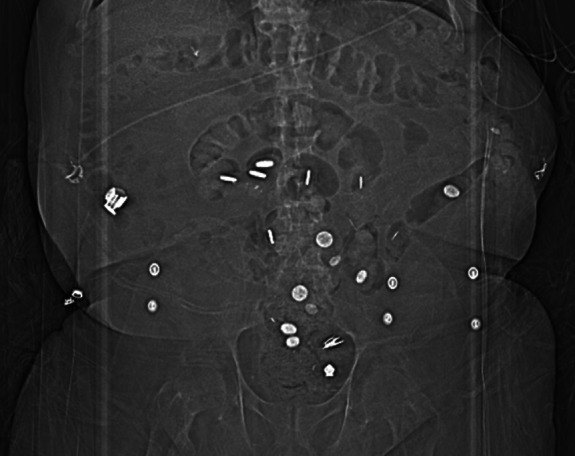

An ESKD Patient with Unusual Findings on Abdominal Imaging.

ESKD患者腹部影像学异常表现1例。